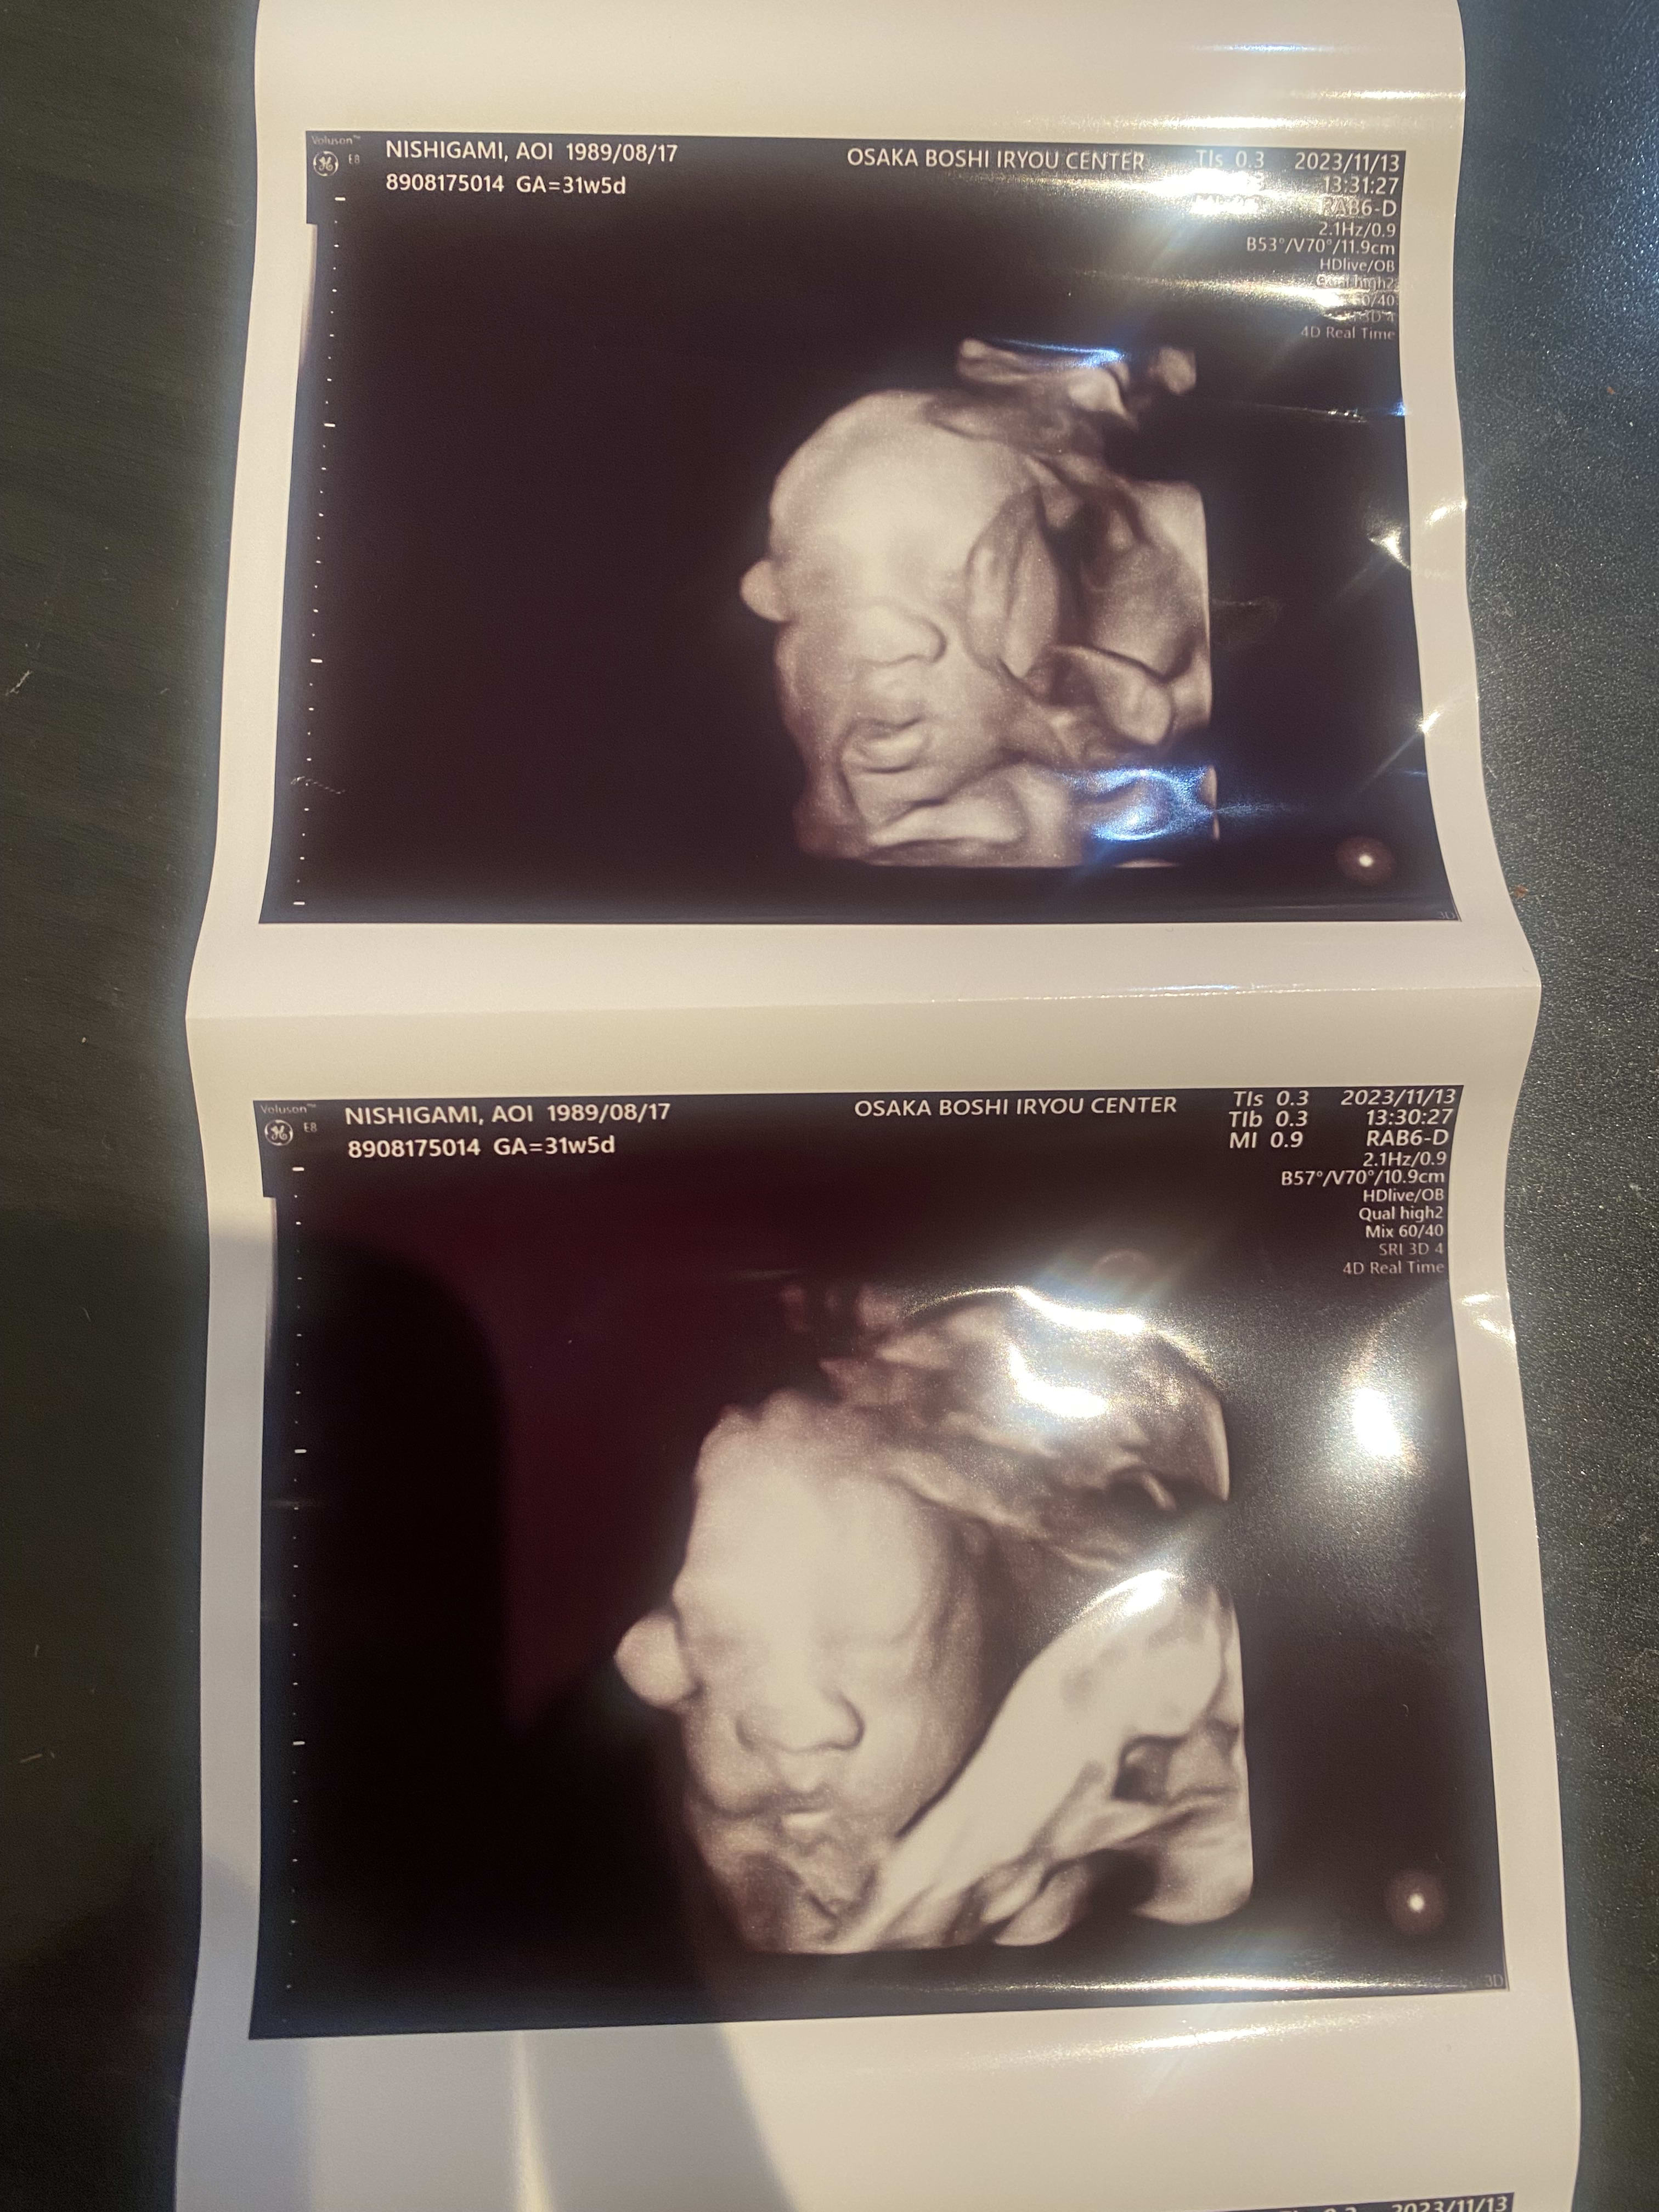

31週のエコー写真。 大阪に帰ってきて初めての病院。2017gで大きいですね、と助産師さんに言われたよ。口をパクパクしていて可愛かった。

13 Nov 2023